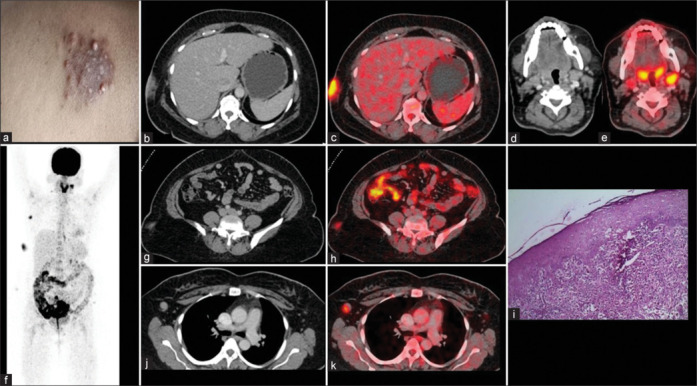

Rosai-Dorfman-Destombes (RDD) disease is also called as sinus histiocytosis and is characterized by enlarged lymph nodes and previously called as non-Langerhans cell histiocytosis. Based on pathologic, molecular, and genetic features, RDD disease has been classified into sporadic noncutaneous (classical nodal, extranodal, neoplasia associated, and autoimmune associated), familial (H syndrome, autoimmune lymphoproliferative syndrome related, and familial NOS), and cutaneous subtypes. Cutaneous RDD disease is not associated with lymphadenopathy or visceral organ involvement. The disease is usually localized and has relatively better long-term prognosis. Presented here is a case of indurated plaque-like skin lesions over the abdomen. 18F-fluorodeoxyglucose (FDG) positron emission tomography-computed tomography scan revealed FDG avid cutaneous-subcutaneous soft-tissue lesions. Histology confirmed the diagnosis of cutaneous RDD disease.